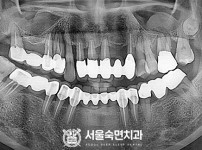

임플란트-전후사진1

임플란트-전후사진2

임플란트-전후사진3

임플란트-전후사진4

임플란트-전후사진5

임플란트-전후사진6

치과를-선택할-때-꼭-확인하세요-서울숙면치과-임플란트-전후사진